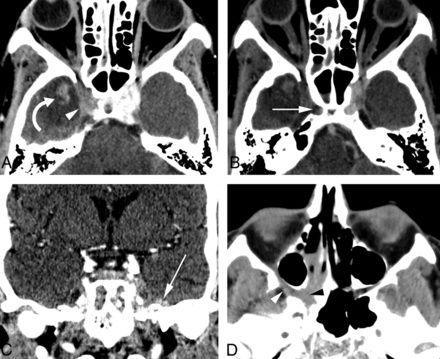

Thirteen variables had 100% specificity for AIFR, but only 5 of these had a sensitivity of >30% (nasolacrimal duct, lacrimal sac, septal ulceration, orbital involvement, and bone dehiscence; Figs 2 and 3). The remaining variables with 100% specificity represented late-stage disease findings (epidural, subdural, abscess, venous thrombosis, arterial thrombosis, cavernous sinus involvement, intraparenchymal extension, and horizontal palate involvement; Fig 4). Variables related to the degree of opacity had relatively poor sensitivity and specificity as binary variables.

Illustration of less commonly described areas of AIFR, including the nasolacrimal duct, lacrimal sac, and nasopharynx. A, Contrast-enhanced axial CT image shows soft-tissue thickening and inflammatory stranding in the area of the left lacrimal sac (white arrow) and in the medial orbit (white arrowhead). The normal right nasolacrimal duct (curved arrow) is identified for comparison. Asymmetric unilateral mucosal disease is also seen in the left ethmoid air cells (asterisk). B, Coronal image again shows thickening and inflammatory change in the left lacrimal sac (white arrow) and medial orbit (black arrowhead). Similar inflammatory changes are seen in the left nasolacrimal duct (white arrowhead). C, Axial CT in a different patient with AIFR with marked asymmetric mucosal thickening of the right nasal cavity (asterisk) and right nasopharynx (arrow). D, Axial contrast-enhanced CT in a third patient with marked asymmetric mucosal thickening in the left nasopharynx (arrow) and subtle inflammatory stranding involving the left parapharyngeal fat (arrowheads).